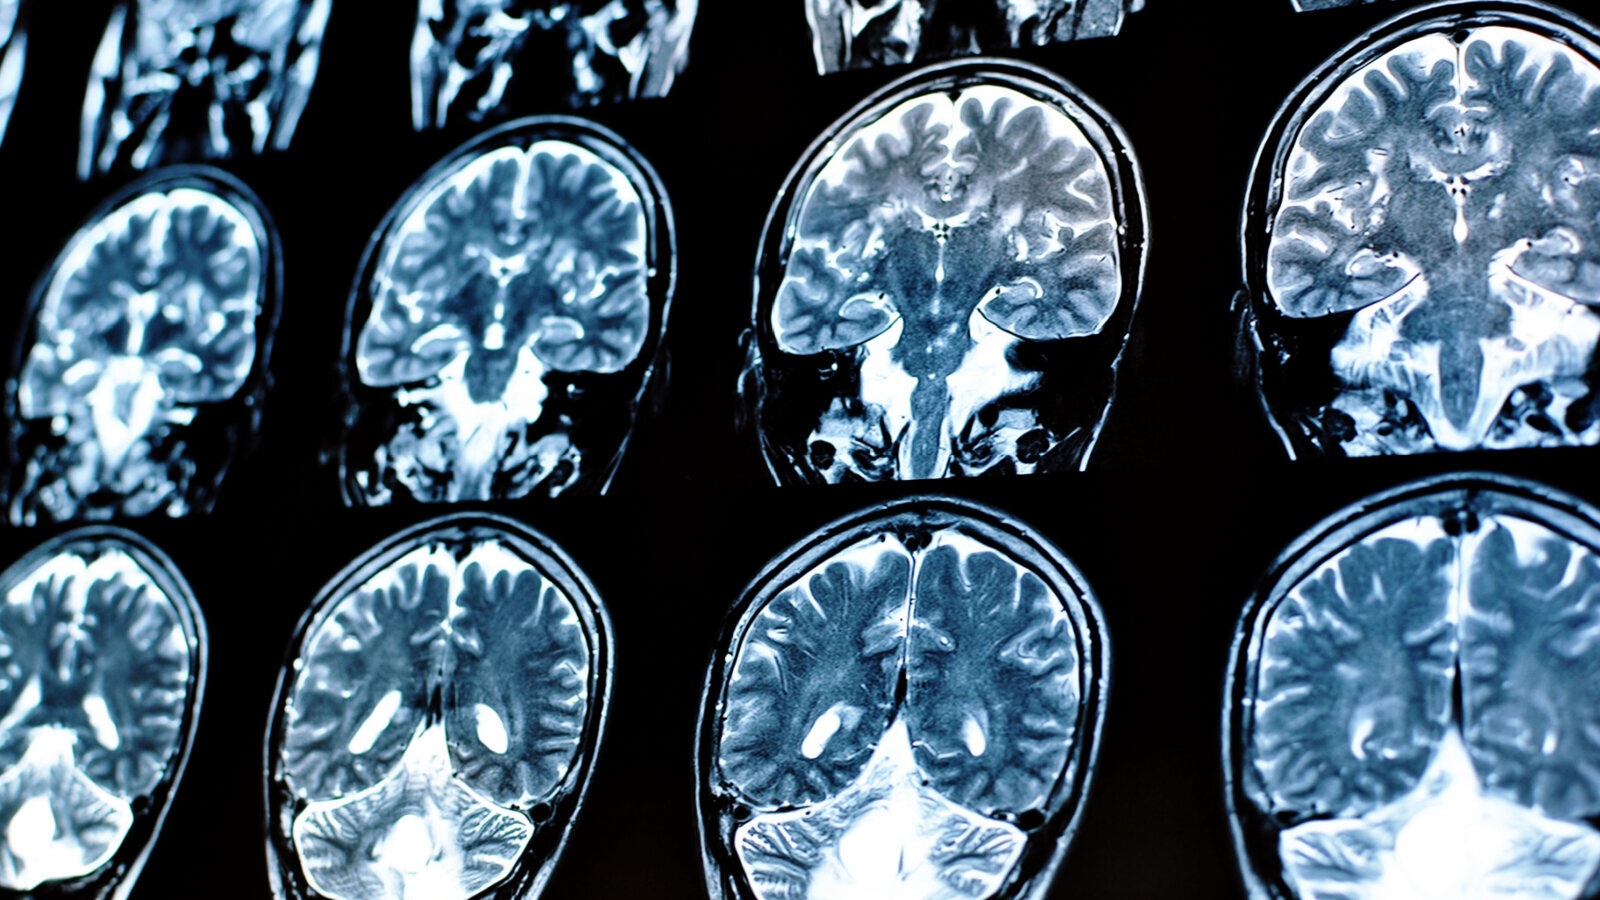

Pošto je bilo malo prethodnih istraživanja o ovoj temi, magnetna rezonanca se sada koristi za pružanje naznaka o tome kako oralno zdravlje može imati uticaj na funkciju mozga. (Fotografija: Alina Bratosin/Shutterstock)

DALAS, SAD: Povećana incidencija cerebrovaskularnih bolesti mogla bi biti povezana sa genetskom predispozicijom za loše oralno zdravlje, prema novoj studiji koju finansira Američko udruženje za srce. Istraživači su koristili prisustvo hiperintenziteta bele materije mozga, koji su akumulirana oštećenja bele materije, kao dokaz cerebrovaskularne bolesti. Dokumentovano putem magnetne rezonancije (MRI), rezultujući skenovi su pokazali da je kod osoba koje su genetski sklone bezubosti ili karijesu došlo do povećanja hiperintenziteta bele materije u mozgu od 24%.

Vodeći autor studije dr Siprijen Rivijer (Dr Cyprien Rivier), istraživač na postdoktorskim studijama na Odeljenju za neurologiju Medicinskog fakulteta Jejla u Nju Hejvenu u Konektikatu, prokomentarisao je u saopštenju za štampu: „Proučavanje oralnog zdravlja je posebno važno jer se loše oralno zdravlje dešava često i faktor je rizika koji se lako može promeniti i eliminisati – svako može efikasno da poboljša svoje oralno zdravlje uz minimalno vreme i finansijska ulaganja.” Dr Rivier je takođe primetio vrednost korišćenja alata za neuroimidžing kao što je MRI za procenu uticaja oralnog zdravlja na funkciju mozga.